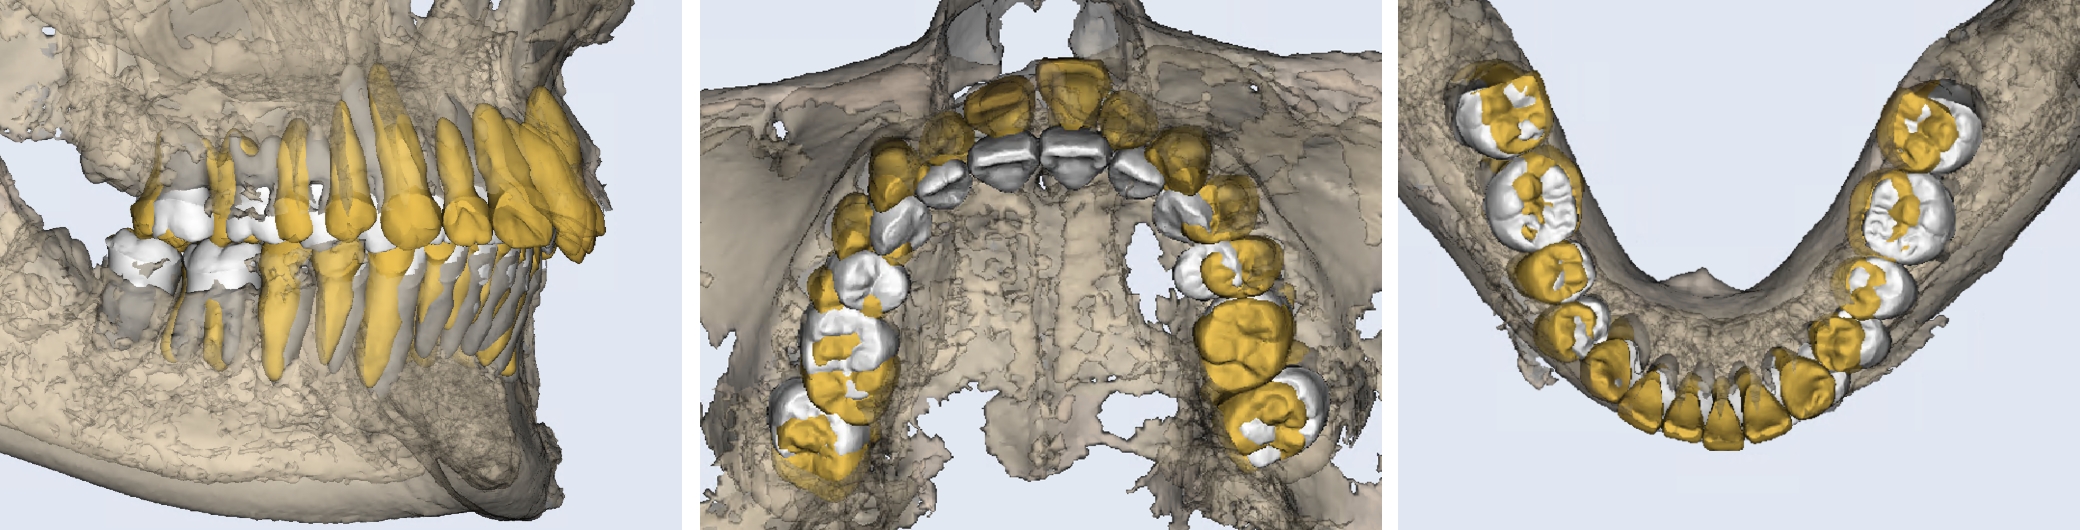

3DCTの治療例

初診とセットアップ重ね合わせ

セットアップと終了時重ね合わせ

治療が終わる頃の歯の位置は、事前に作成した3Dセットアップで想定した「骨の中で無理のない位置」とほぼ一致しています。※症例により個人差があります。